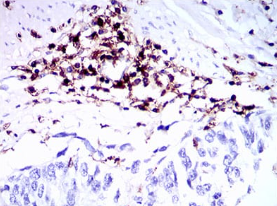

IHC    1/200 - 1/1000